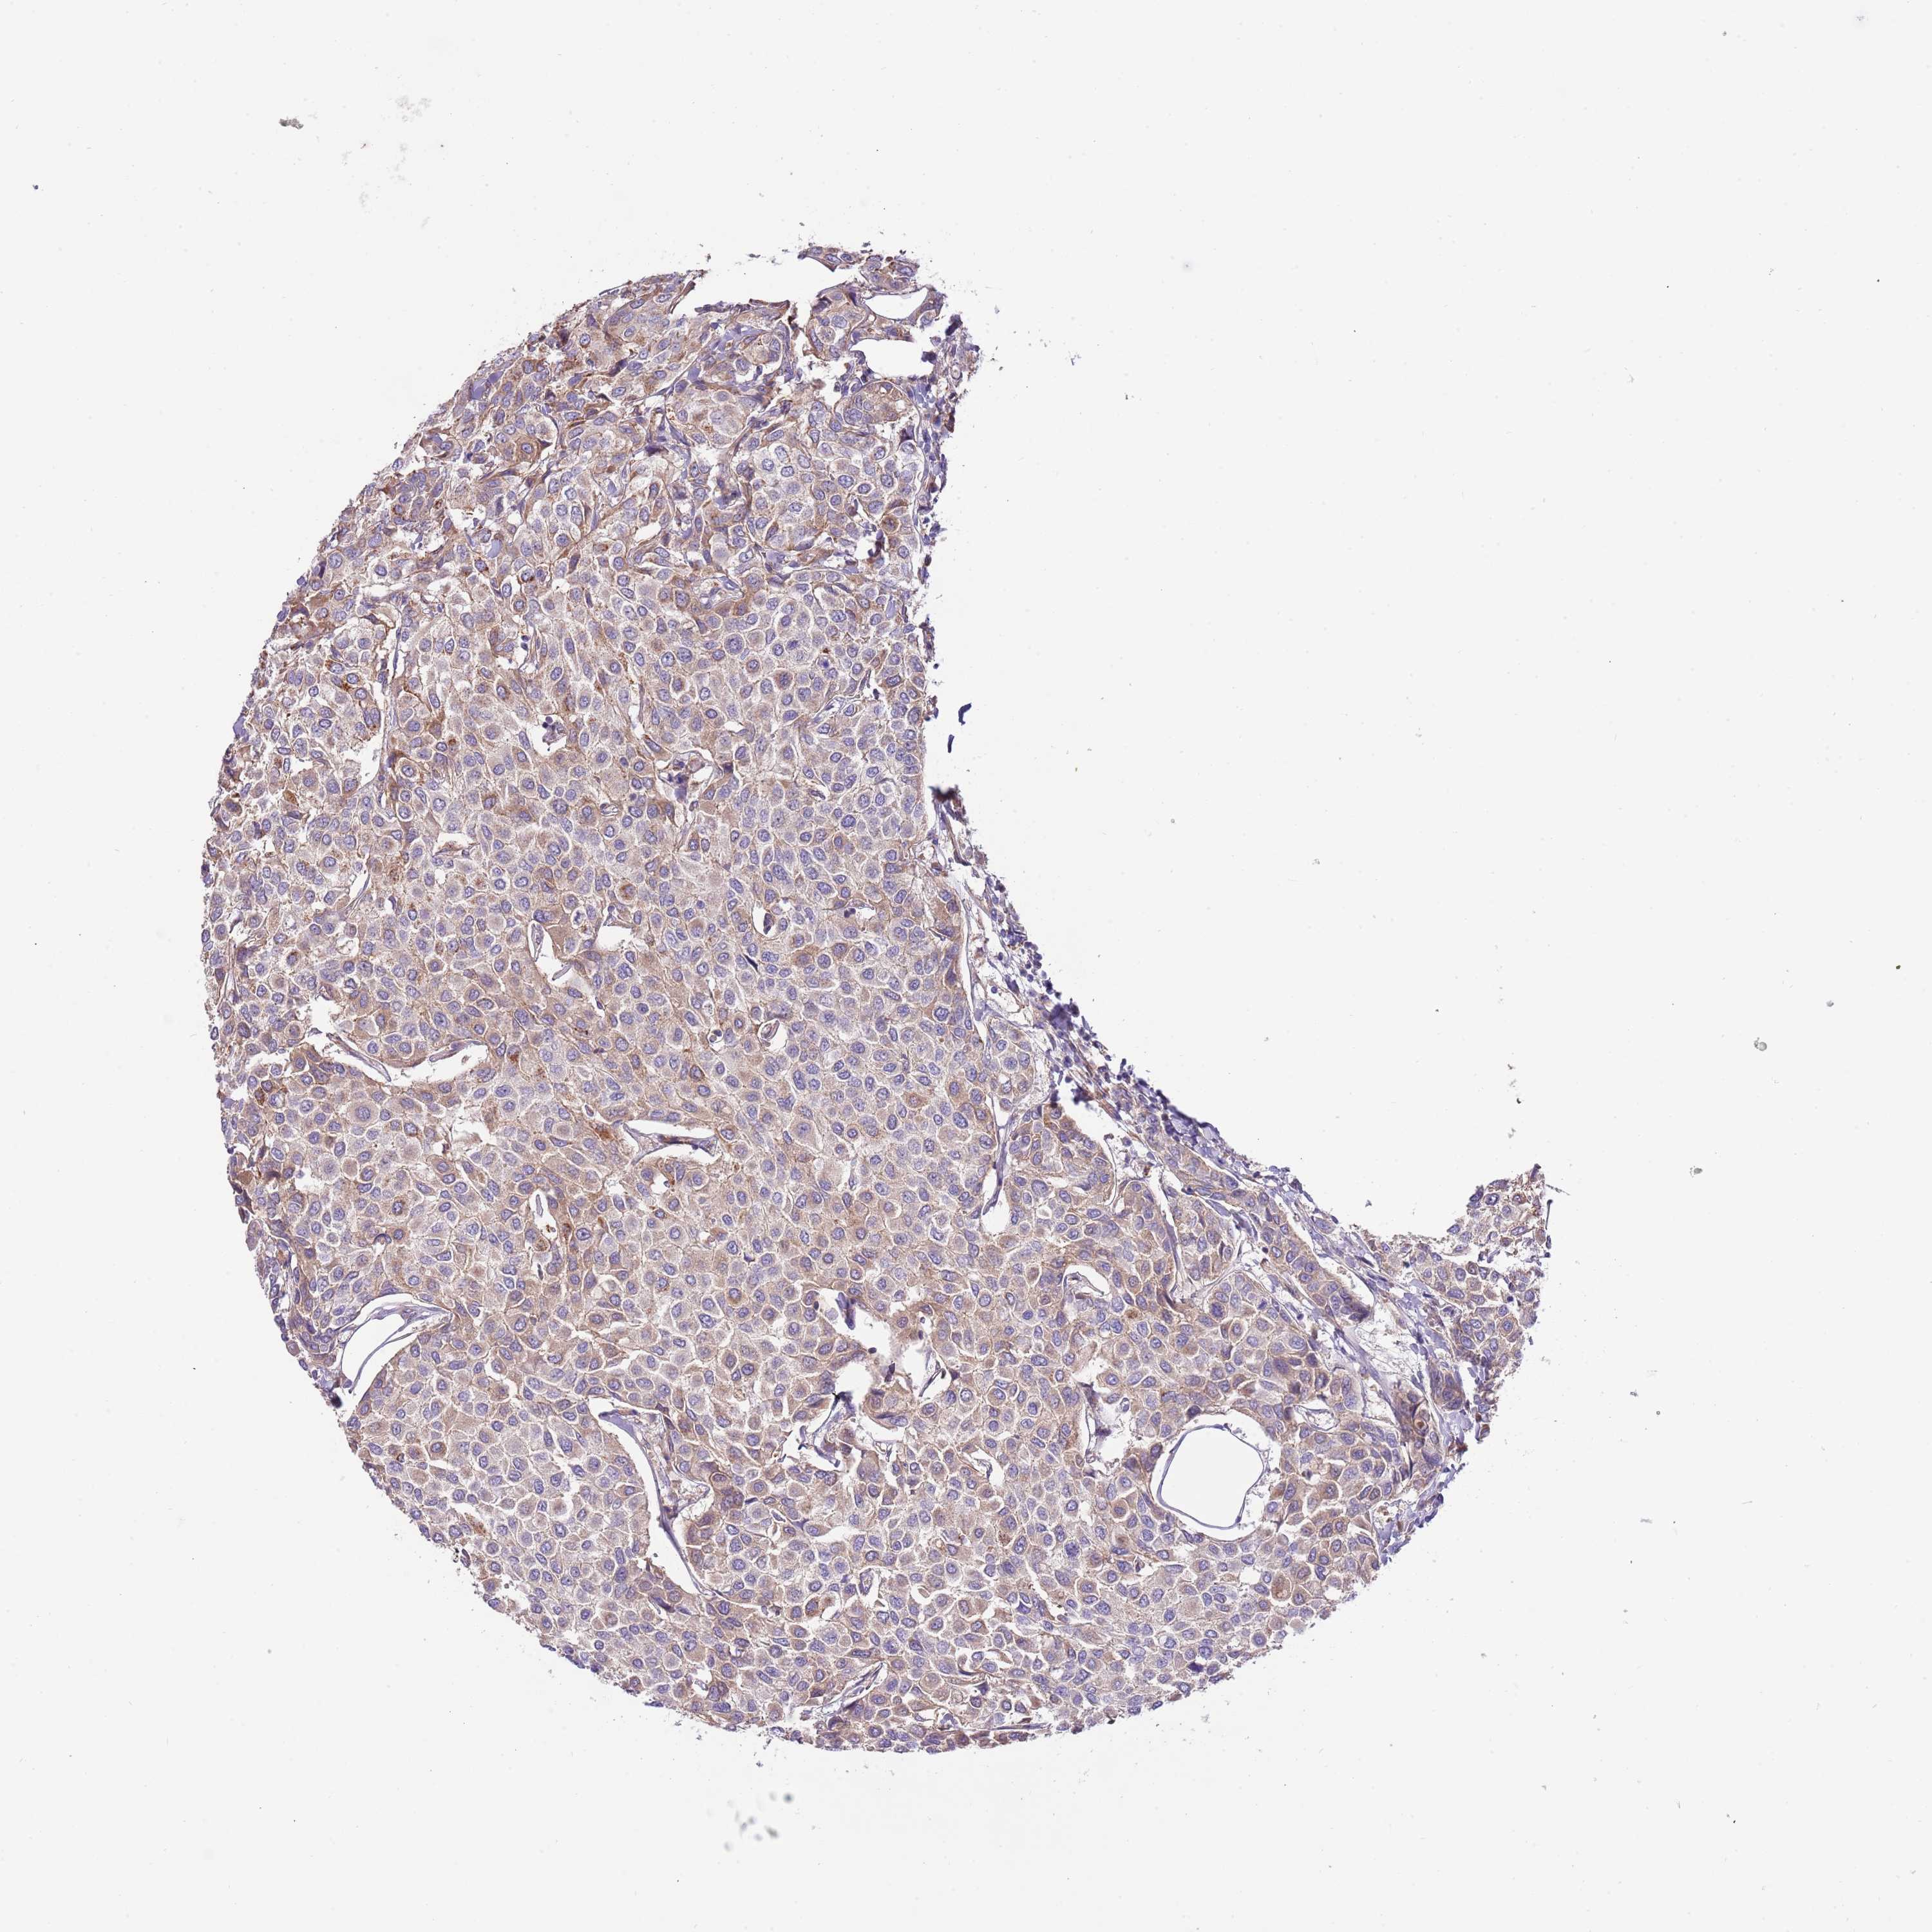

CANCER BREAST CANCER Show tissue menu

BRCA TCGA BRCA VALIDATION PROTEIN EXPRESSION

Breast cancer

Human cancer

Breast invasive carcinoma